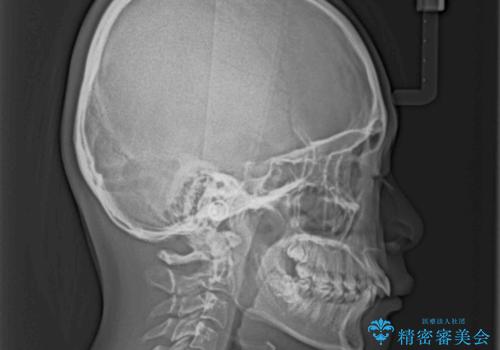

- 下唇に上顎前歯の跡がつくくらいに突出した前歯とデコボコを気にして来院された患者様です。

口元の突出感改善のため、上下左右の第一小臼歯4本を抜歯し、ワイヤー装置にて矯正治療を行うこととしました。

それほど口元の突出感が強いわけではありませんでしたが、下唇に前歯引っかかる感触が気になっていたため、抜歯矯正を行うこととしました。

上下前歯の被蓋が理想通りに改善され、患者様には大変満足していただけました。